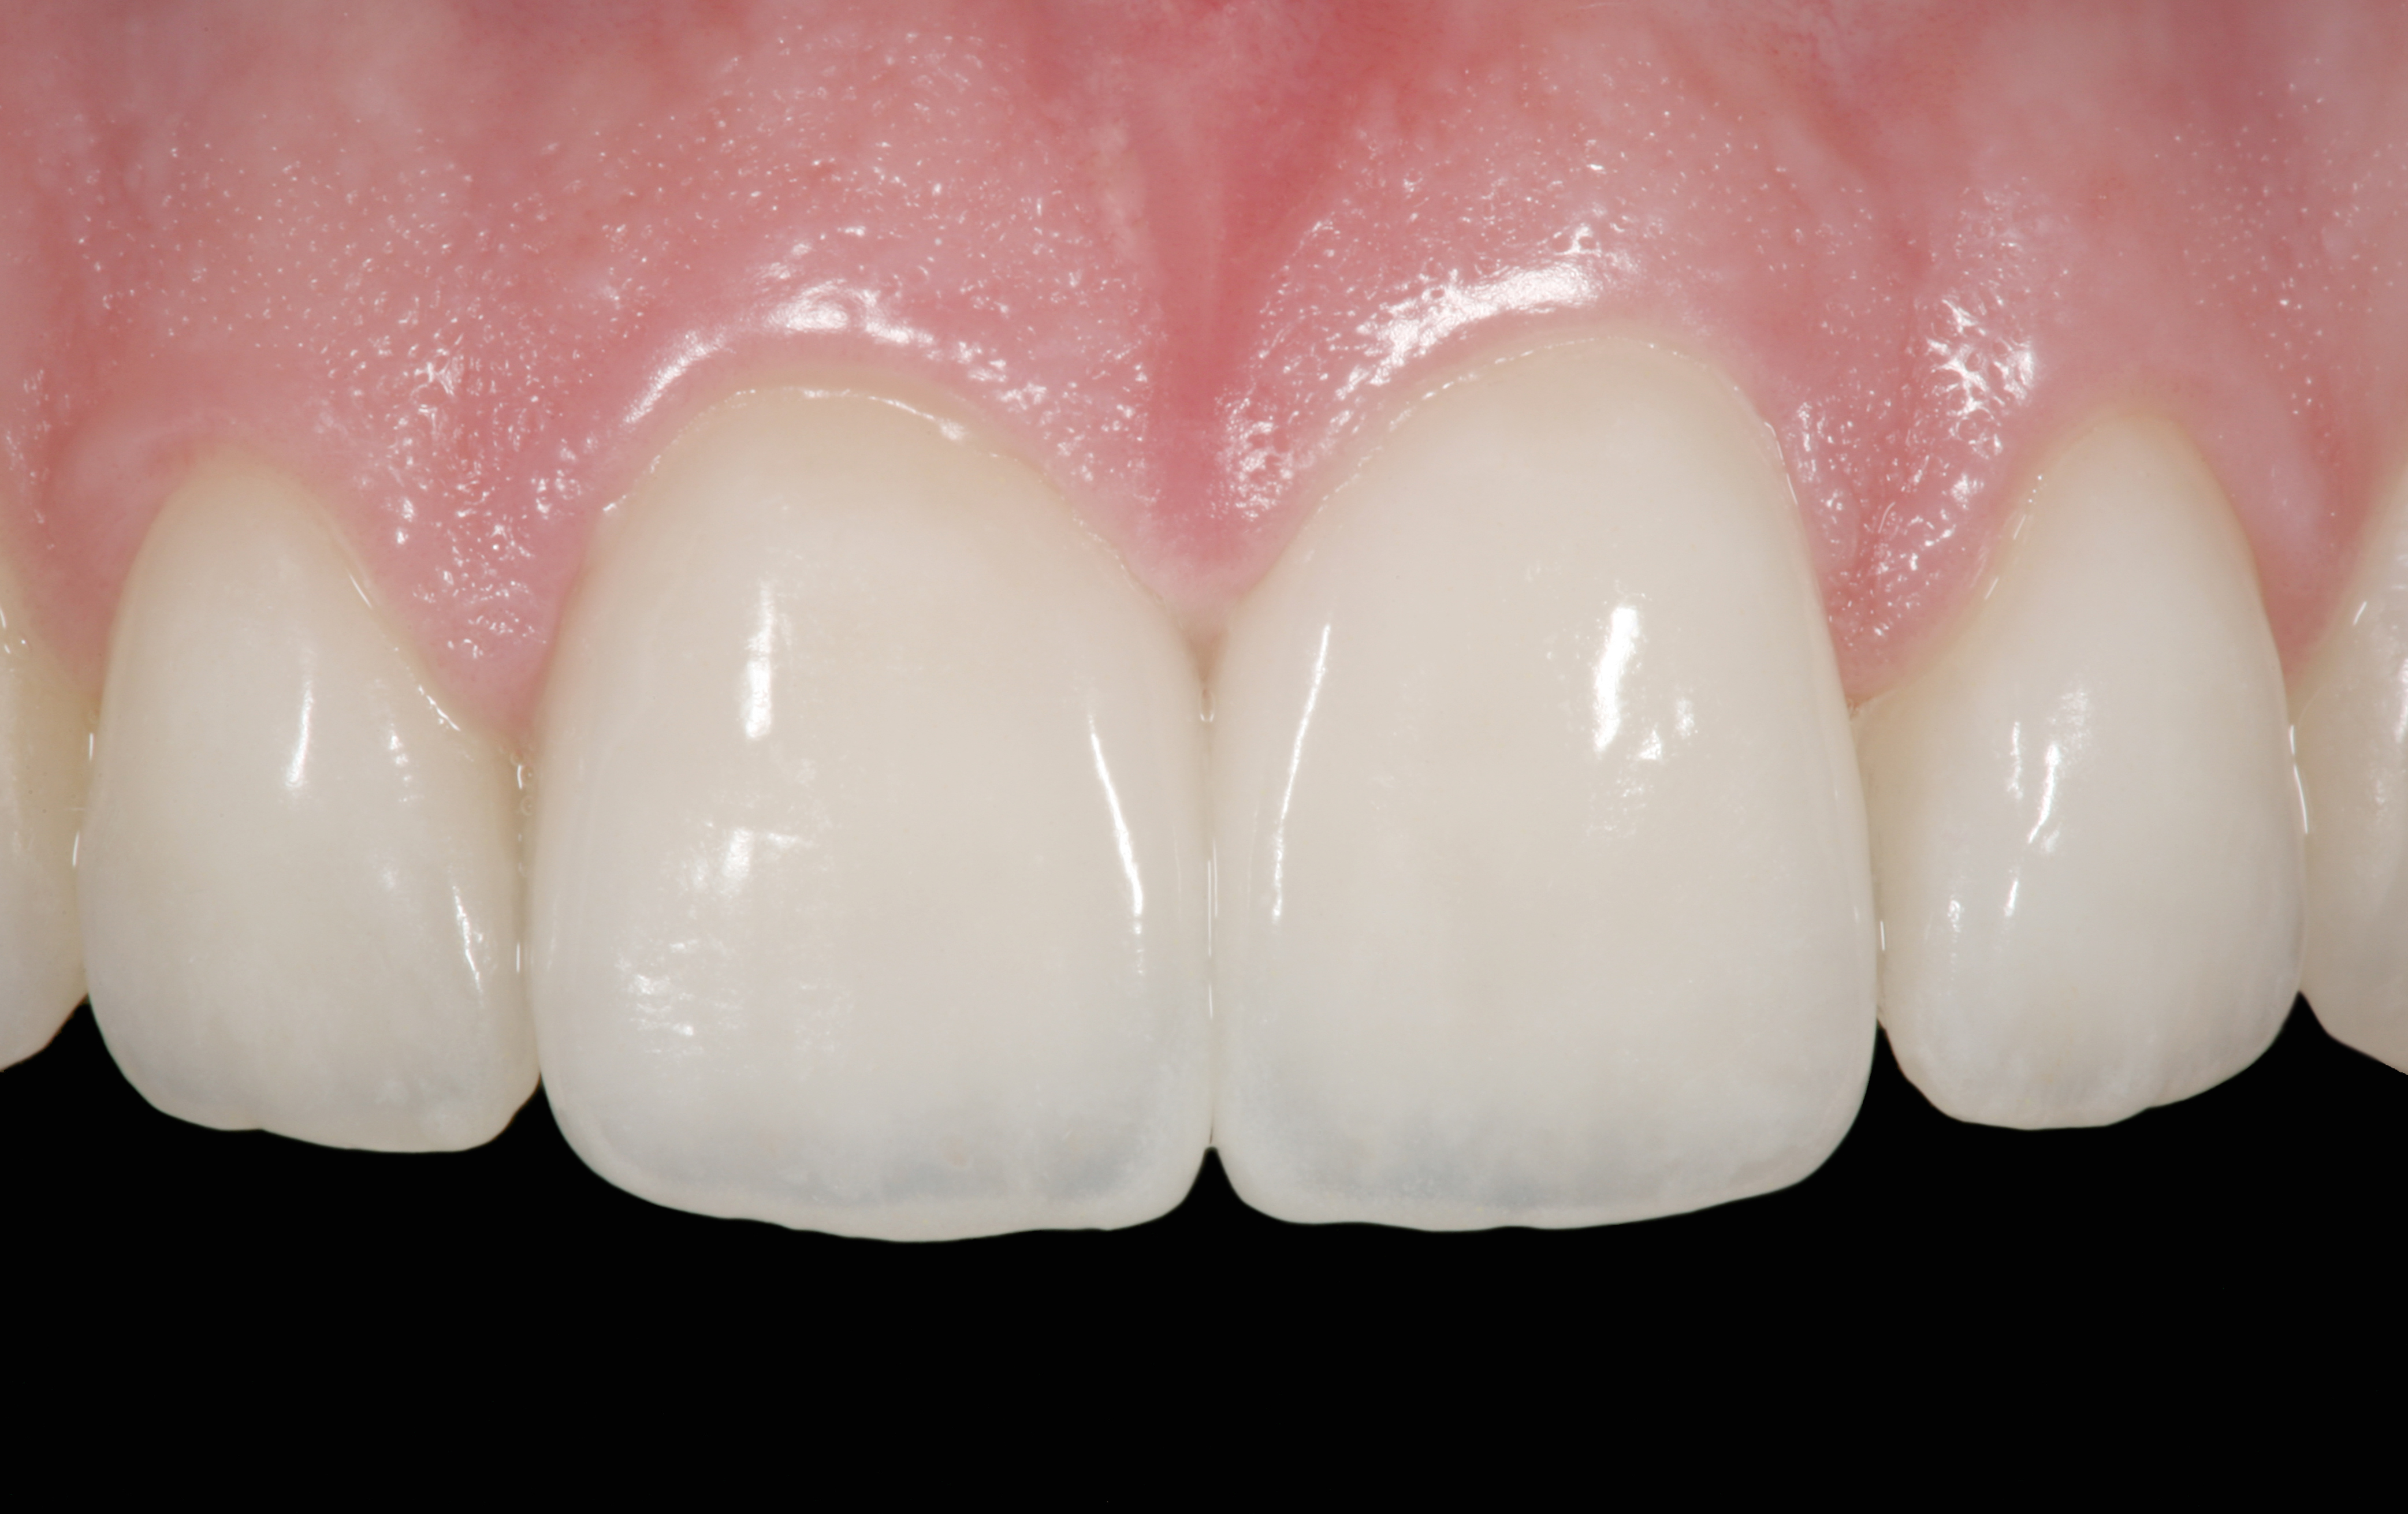

The clinical application of this protocol is illustrated in a patient situation where laminate veneers were placed on four maxillary incisors to replace lost tooth structure and restore function and esthetics. The failing restorations were removed, followed by a conservative veneer preparation (Figure 1 and Figure 2). The bonding surfaces of the feldspathic porcelain veneers were acid-etched with hydrofluoric acid for 2 minutes (Figure 3) and thoroughly rinsed. Then a silane coupling agent was applied (Figure 4). Figure 5 demonstrates the situation after bonding the veneers to the teeth with a composite resin luting agent.

A patient in her 60s wanted to improve her smile but declined orthodontic treatment in favor of porcelain veneers (Figure 13). However, addressing her 8-mm pocket was the first step. The practitioner created biologically clean root surfaces using ultrasonic open-flap debridement, finishing burs, and manual tool instrumentation. Next, a mineralized freeze-dried bone allograft saturated in platelet-derived growth factor (Figure 14) using chemotaxis pulled the stem cells capable of regeneration into the site where repopulation was needed. Prior to closure, a resorbable membrane, polylactic acid-guided tissue regeneration—known for periodontal regeneration—was used (Figure 15). At 10 weeks, adequate healing had occurred. The patient at 6 and 10 weeks showed continued healing. Although some postoperative recession was evident, probing depths were less than 2 mm, and the patient was referred back to the restorative dentist for restorative therapy. As of this writing, she has not lost any teeth and is periodontally stable (Figure 16).

The final restorative situation. (Restorative therapy by Dr. B. Wilk, Chalfont, PA.)

Figure 16